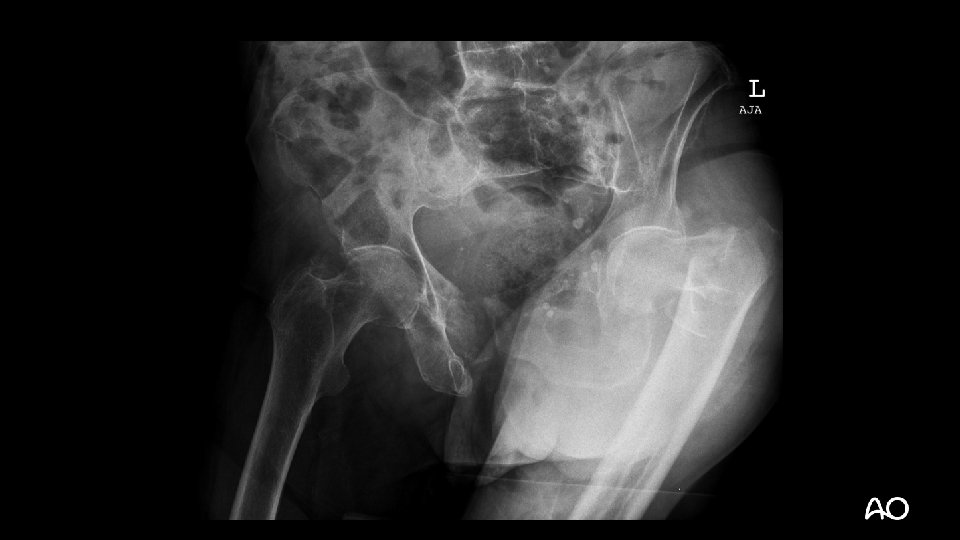

Case description • 82 -year-old woman • Stumbled on carpet at home • Has lived alone there for 2 months following the death of her husband • Was mobile with walker • Parker-Score of 5, ADL Barthel 75 pts, in an older chart a Mini. Mental-Score of 23 is mentioned

Preoperative examinations • • • X-rays Thoracic X-ray ECG Lab Seen by internal specialist • Intermediate risk • Seen by anesthesiologist • ASA III